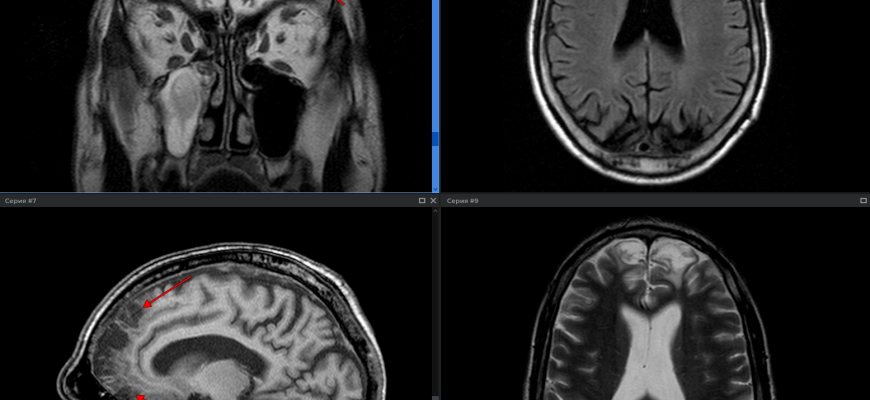

Искусственный Интеллект на Страже Здоровья: Наш Опыт Разработки ИИ для Анализа МРТ В современном мире технологии проникают во все сферы нашей жизни, и